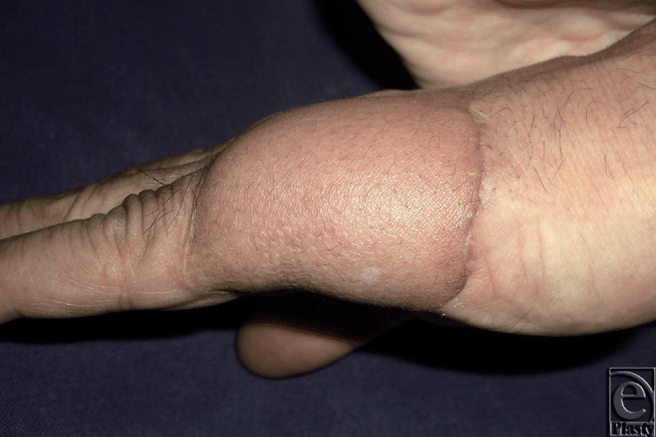

We would like to present the use of the S-plasty method for revising the inset of a flap. Occasionally, the inset of a flap results in a depressed scar at the junction between the flap and the normal skin. This scar is further accentuated in a bulky flap. An S-plasty was designed over the depressed portion of the scar (Fig. 1). The S-plasty involves making a series of small-wave like incisions that are approximately 0.5 to 1.0 cm in length. The scar measured 6.5 cm preoperatively and the immediate postoperative length was 8 cm. Figure 2 shows the late postoperative appearance.

| Figure 2. Postoperative appearance at 6 months. |